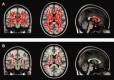

Results: Widespread cortical and deep WM area differences characterized by increased FA values were seen in the AOAMS compared with POMS group (P < 0.05, TFCE corrected). Significantly increased FA values of posterior WM areas were detected in the AODMS compared with POMS group (P < 0.05, TFCE corrected).

Conclusion: Increased FA values in WM areas of the AOMS compared with the POMS patients suggest that diffuse WM microstructure changes are more attributable to age of onset than a simple function of disease duration and age.